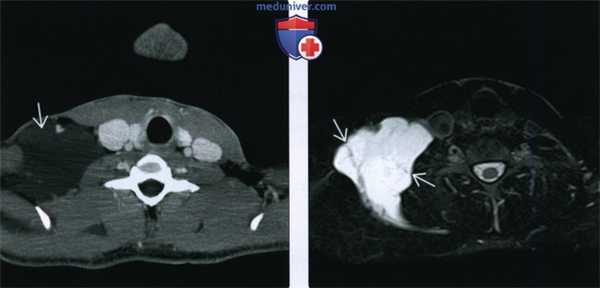

(Слева) При аксиальной КТ с КУ у мужчины 25 лет визуализируется баллотирующее объемное образование в надключичной области.

(Справа) При аксиальной МРТ Т2 FS у этого же пациента в задних отделах шеи визуализируется лимфатическая мальформация, принимающая форму окружающих ее структур, с сигнальными характеристиками, соответствующими жидкости. Обратите внимание на перегородки внутри образования, видимые на МРТ, но не визуализирующиеся на КТ с КУ.